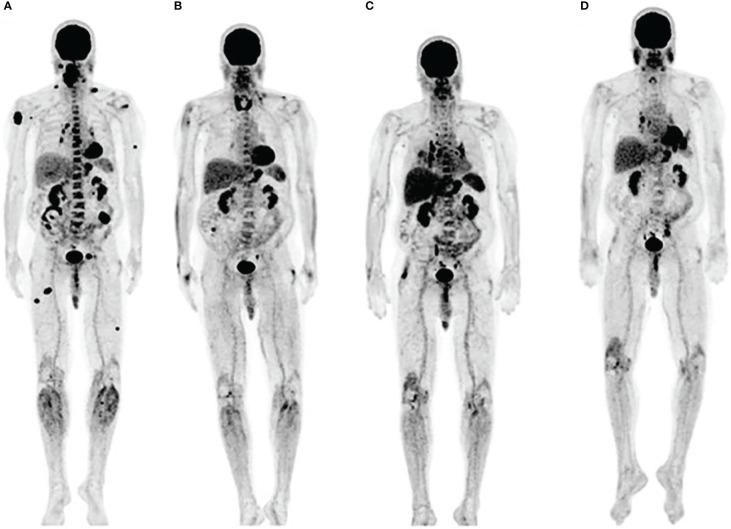

Unique patterns of response to immune checkpoint inhibitor therapy, discernable in the earliest clinical trials, demanded a reconsideration of the standard methods of radiological treatment assessment. Immunomonitoring, that characterizes immune responses, offers several significant advantages over the tumor-centric approach currently used in the clinical practice: 1) better understanding of the drugs' mechanism of action and treatment resistance, 2) earlier assessment of response to therapy, 3) patient/therapy selection, 4) evaluation of toxicity and 5) more accurate end-point in clinical trials. PET imaging in combination with the right agent offers non-invasive tracking of immune processes on a whole-body level and thus represents a method uniquely well-suited for immunomonitoring. Small molecule metabolic tracers, largely neglected in the immuno-PET discourse, offer a way to monitor immune responses by assessing cellular metabolism known to be intricately linked with immune cell function. In this review, we highlight the use of small molecule metabolic tracers in imaging immune responses, provide a view of their value in the clinic and discuss the importance of image analysis in the context of tracking a moving target.

独特的免疫检查点抑制剂治疗反应模式,在最早的临床试验中就已经显现,这要求重新考虑放射治疗评估的标准方法。免疫监测可以描述免疫反应,与目前临床实践中使用的以肿瘤为中心的方法相比具有几个显著优势:1)更好地了解药物的作用机制和治疗耐药性;2)更早地评估对治疗的反应;3)患者/治疗选择;4)评估毒性;5)临床试验中更准确的终点。PET 成像与合适的药物联合使用,可以在全身范围内非侵入性地跟踪免疫过程,因此是一种非常适合免疫监测的方法。小分子代谢示踪剂在免疫 PET 研究中被忽视,但它们可以通过评估与免疫细胞功能密切相关的细胞代谢来监测免疫反应,为我们提供了一种新的方法。在这篇综述中,我们强调了小分子代谢示踪剂在免疫反应成像中的应用,探讨了它们在临床中的价值,并讨论了在跟踪移动目标的背景下图像分析的重要性。